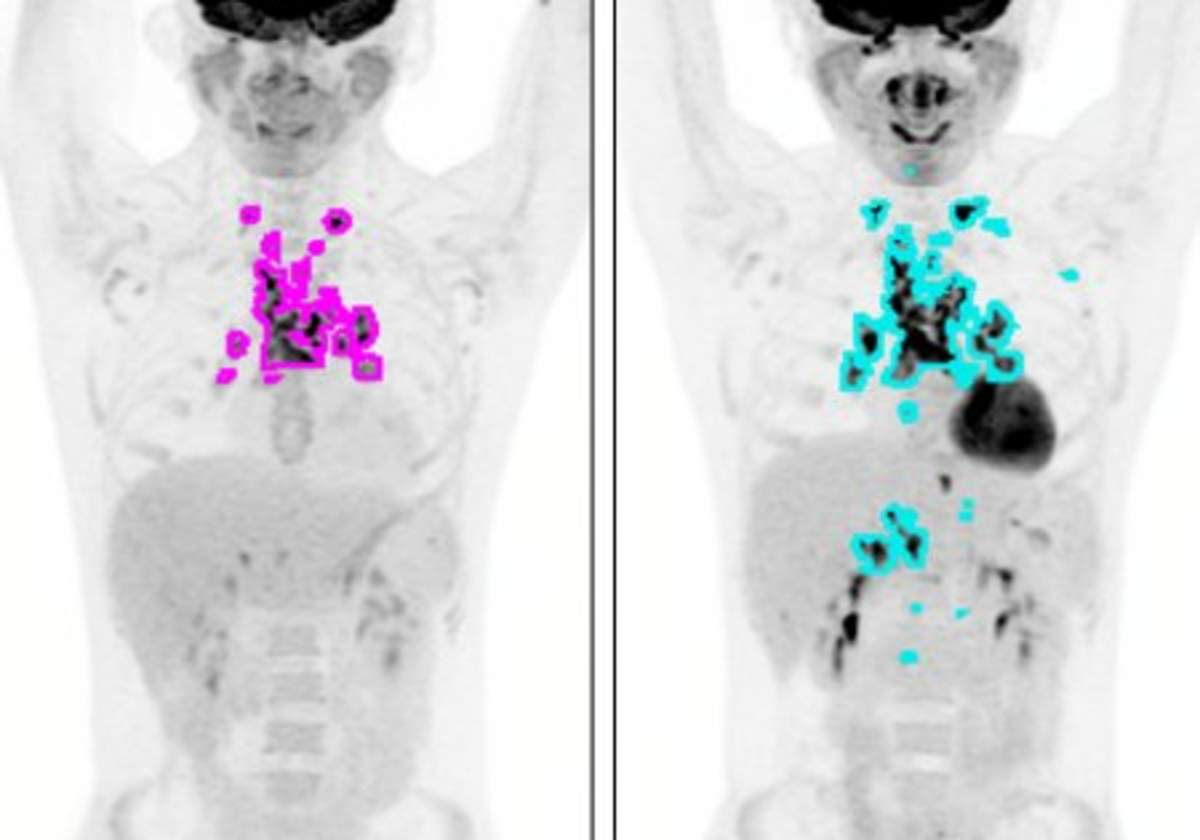

Molecules Free Full Text Positron Emission Tomography Pet Radiopharmaceuticals In Multiple Myeloma Html